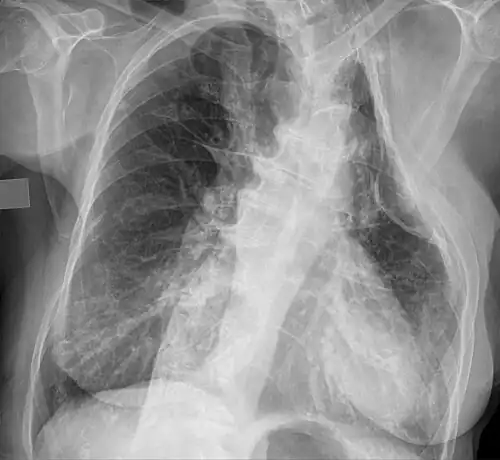

Eine Thorakoplastik ist ein operativer Eingriff, bei welchem Rippen oder Rippenteile einer Seite des Brustkorbs operativ entfernt werden, um die Lunge oder Teile der Lunge zum Kollabieren zu bringen.

Die operative Mortalität betrug in der Vergangenheit bis zu 10 %. Die Folgen des Eingriffes konnten von einer Skoliose über verminderte Beweglichkeit bis zu Atemstörungen reichen.